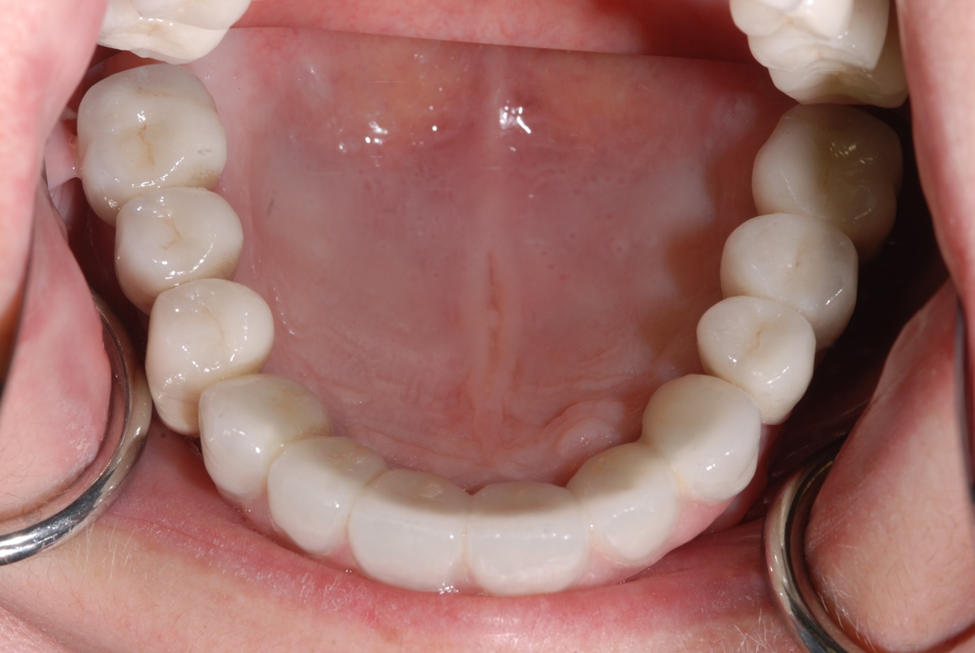

Figure 5a. Occlusal view of implants placed showing excellent keratinized tissue and good thickness.

Figure 5c. Occlusal view of porcelain to metal prosthesis.